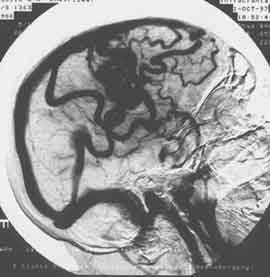

Рис. 3. Дигитальная субтракционная ангиограмма того же больного. Венозная фаза, правая боковая проекция. Четко визуализируется артерио-венозная мальформация в правой теменной области, множественные резко расширенные дренажные вены, синусы твердой мозговой оболочки.